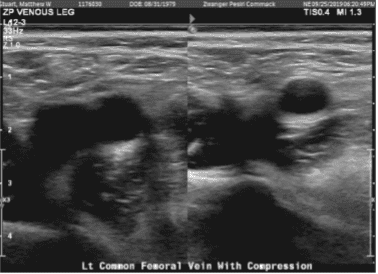

Extremidad inferior venosa Doppler izquierda

Existen hallazgos compatibles con trombosis venosa profunda de la pierna izquierda. En concreto, hay hallazgos consistentes con trombosis venosa profunda que afecta al sistema venoso tibial posterior visualizado. La apariencia es compatible con una trombosis venosa profunda aguda.